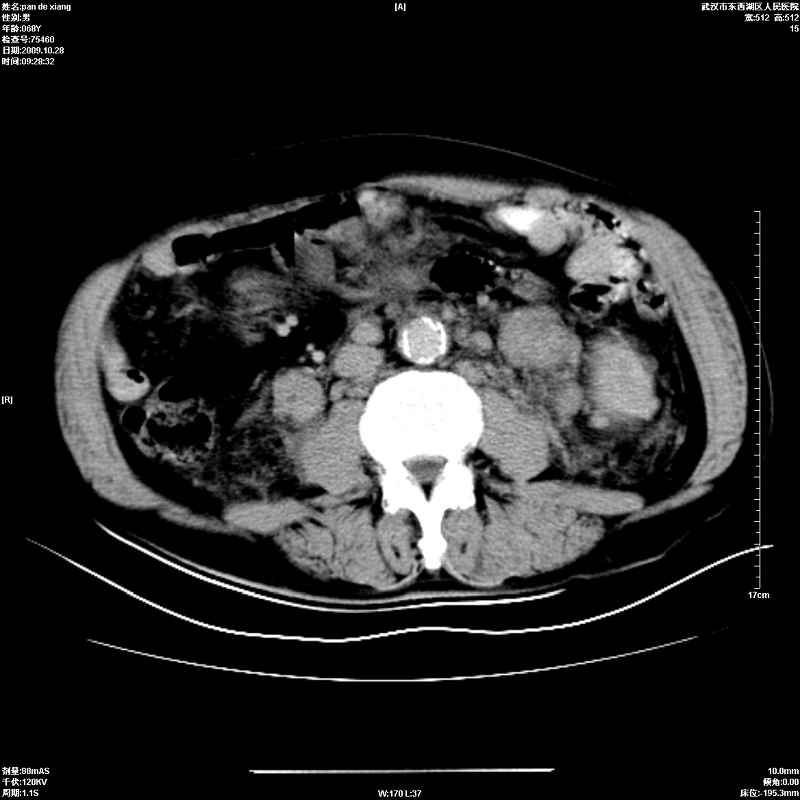

以下是引用杀毒软件在2009-10-28 20:41:00的发言:[br]结合临床考虑---白血病双肾改变或淋巴瘤。

以下是引用zxl51642在2009-10-29 9:59:00的发言:[br]结合临床“单克隆免疫球蛋白血症”,考虑双肾为继发损害并肾功能不全(尿中大量igg及少量iga、igm等大分子免疫球蛋白滤出所致继发损害),椎前软组织肿块为髓外造血。与浆细胞瘤有区别,平扫时有战友说的很清楚。